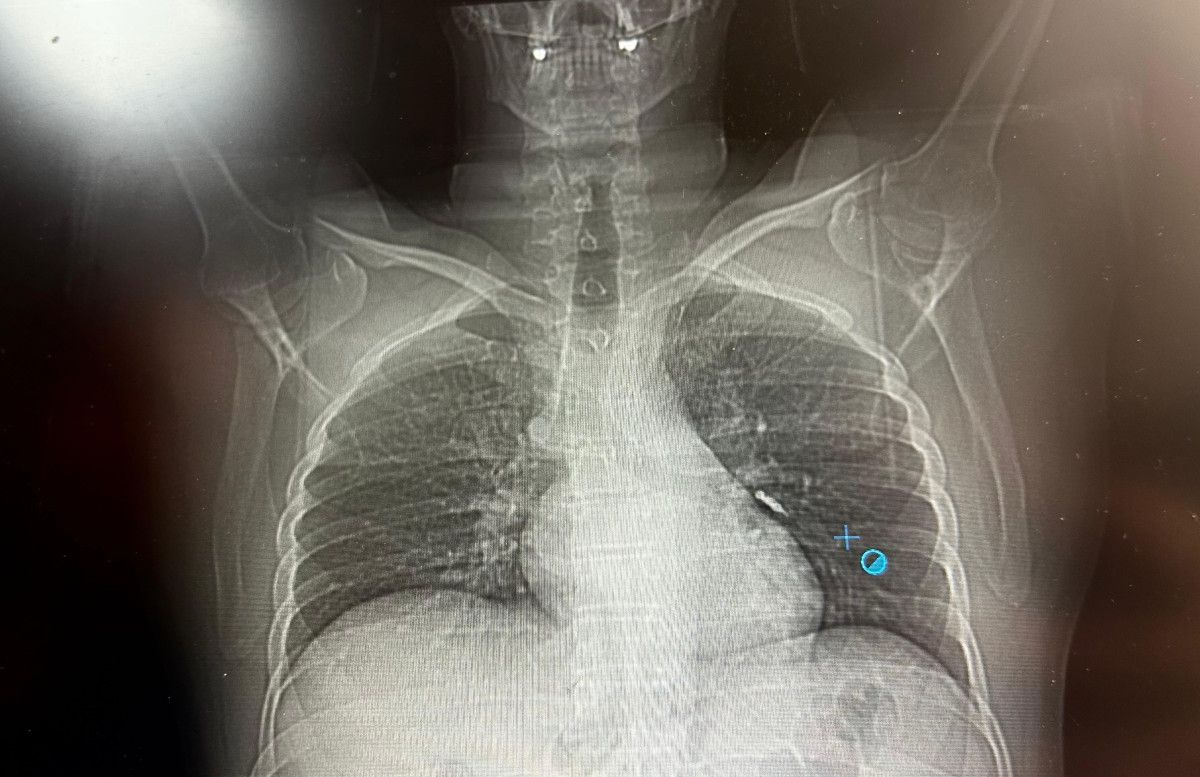

Daha sonra hasta için yeniden bronkoskopi planladıklarını ancak bu süreçte hasta şiddetli bir öksürük geçirdiğini anlatan Aksoy, "Şiddetli öksürük sonrası yapılan kontrol akciğer filminde implant vidası görünmedi.

Bunun üzerine toraks ve batın BT (bilgisayarlı tomografi) görüntülemesi istedik. Sonuçlarda implantın akciğerden çıktığı ve vücutta herhangi bir yerde bulunmadığı tespit edildi" diye konuştu.